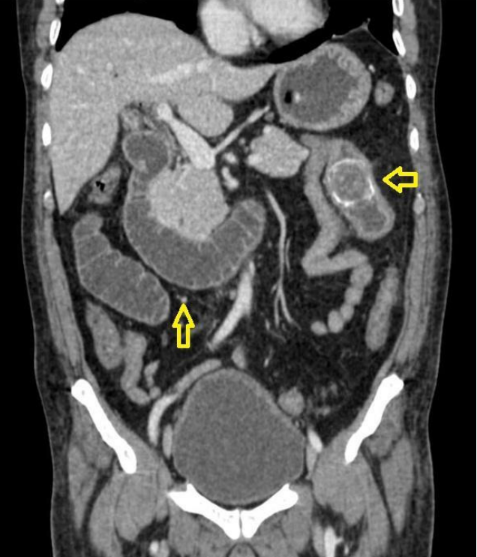

En dicha institución se revalora al paciente, evidenciando al examen físico mal estado general, consciente, orientado, con signos de dificultad respiratoria y desaturación al aire ambiente hasta 70%, saturación hasta 92% con oxígeno por máscara con reservorio a 8 l/min, piel y mucosas moderadamente secas, normocoloreadas, pulmones con murmullo vesicular disminuido con estertores y roncus diseminados en ambos campos pulmonares, abdomen levemente distendido, con ruidos hidroaereos (+) hipoactivos, blando, doloroso a la palpación profunda en mesogastrio, sin datos de irritación peritoneal, tacto rectal con esfínter normotónico, ampolla rectal vacía y dedo de guante explorador limpio, siendo el resto del examen conservado. Se obtienen estudios complementarios de laboratorios en sangre que reportan: leucocitosis de 10 640/ml, con neutrofilia del 88 %, Hb 12 g/dl (previo de 15,2), normocítica, normocrómica, Hto 34,8 %, hipoproteinemia con hipoalbuminemia severa con proteínas totales de 4,2 g/dl y albumina de 2,1 g/dl, e hipokalemia leve con K de 3,0 mEq/L, además de gasometría arterial que evidenciaba alcalosis metabólica parcialmente compensada con acidosis respiratoria, con insuficiencia respiratoria aguda hipoxémica moderada (PaFiO2 170), y resto de laboratorios del hemograma, coagulograma, glicemia, pruebas renales y hepatograma dentro de parámetros normales. Se obtiene a la vez Rx de tórax PA y abdomen AP de pie, evidenciando en el primero imágenes radiopacas de infiltrado alveolo-intersticial diseminadas en ambos campos pulmonares a predominio del lado izquierdo, y en la segunda, asas de intestino delgado dilatadas con imagen sugestiva de pila de monedas y niveles hidroaéreos a predominio del lado izquierdo (Figura 1). Tras la obtención de estos exámenes y en el contexto del paciente se han tomado en cuenta los diagnósticos diferenciales de obstrucción intestinal vs hemorragia digestiva alta, este último según la institución inicial que realizó la referencia, que indicaba la presencia de vómitos porráceos y el evidente descenso de la Hb en 3 puntos, por lo que se continúa con la indicación de endoscopia digestiva alta la cual reporta: “Datos de obstrucción intestinal alta (debito de retención proveniente de segunda y tercera porción duodenal) (Figura 2), sospecha de metaplasia columnar de esófago, gastritis crónica superficial de antro, estudio parcialmente satisfactorio (por segmentos con debito retentivo no valorables)”. Con estos hallazgos se refuerza mucho más la primera hipótesis, pero llama la atención que un paciente sin antecedentes quirúrgicos abdominales presente datos de obstrucción intestinal, además de tratarse de un paciente con un cuadro clínico atípico, y que al momento no había podido ser resuelto bajo medidas conservadoras, por lo que se decide solicitar estudios ampliados extrainstitucionales, como una tomografía axial computarizada (TAC) de abdomen con contraste de forma urgente; tras gestionar la misma, se obtiene reporte que indica (Figuras 3 y 4): “Hallazgos tomográficos compatibles con íleo biliar (imagen de cálculo de 4 x 3,2 cm con áreas de calcificación en su pared a nivel de yeyuno proximal), probable fístula bilio-digestiva (colecistoduodenal), neumobilia, pequeños quistes renales simples bilaterales, hallazgos de la porción valorable de tórax sugerente de proceso infeccioso de etiología viral sugestivas de COVID-19”. Con ello se solicita la valoración por el servicio de cirugía que, en misma fecha de ingreso, realiza procedimiento quirúrgico de laparotomía exploradora, enterotomía, extracción de cálculo y enterorrafia, con diagnóstico postoperatorio de “Obstrucción intestinal alta, íleo biliar, neumonía por SARS-COV2, hiperplasia prostática”, describiendo en los hallazgos operatorios un cálculo de aproximadamente 4 x 4 cm que ocupaba la totalidad de la luz yeyunal a +/- 60 cm del ángulo de Treitz.

En relación a los hallazgos imagenológicos, la imagen en pila de monedas sigue teniendo alto valor diagnóstico en patologías obstructivas del intestino delgado como es en el caso nuestro, al igual que menciona Carpio-Deheza G5 en su publicación de abdomen agudo quirúrgico. En mención a imagenología se recomienda una adecuada valoración de los estudios iniciales que en sospecha de íleo biliar podrían ayudar al diagnóstico y evidenciar la conocida Triada de Rigler, que hace mención de la conjunción en la radiografía de abdomen de pie de: neumobilia, asas de intestino delgado dilatadas y la visualización directa o indirecta de un cálculo en intestino delgado, y en ocasiones, el cambio de posición del lito en radiografías de control. En la revaloración del caso de nuestro paciente se evidencia dos de estos signos específicos, asas de intestinos delgado dilatadas y una tenue imagen sugerente de neumobilia, siendo el hallazgo de dos de los signos de la triada de Rigler patognomónicos de íleo biliar según Aguila-Gomez MV; es así, que el uso de ésta puede ayudar y prescindir de elementos no coste-accesibles en algunos casos8.